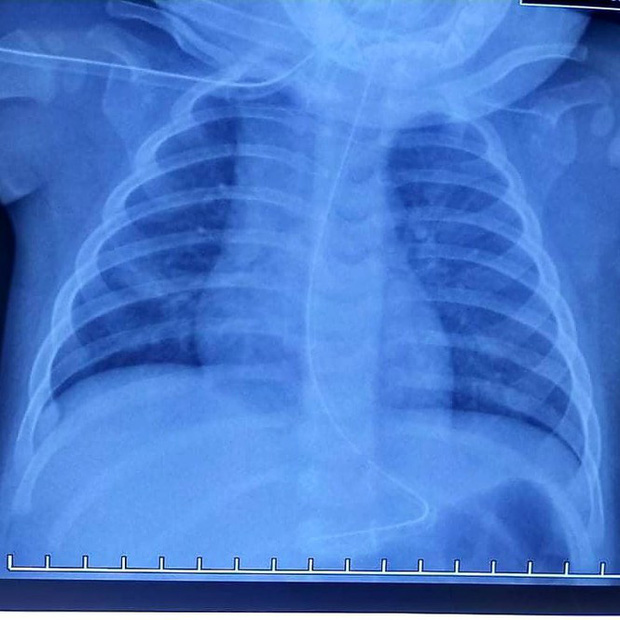

Sau khi thăm khám, chụp x-quang và hội chẩn, các bác sĩ cấp cứu và hô hấp tại BV nghi ngờ bé hóc dị vật, dị vật tắc nghẽn một nhánh phổi nên gây ứ khí toàn bộ nửa trên phổi phải nên đã phối hợp cùng các bác sĩ gây mê tiến hành nội soi cho bé.

Trong khi nội soi, TS.BS Trịnh Hồng Nhiên, Trưởng khoa Hô hấp, Trưởng ekip Nội soi hô hấp đã phát hiện ra dị vật là đốt xương lươn nằm bít hoàn toàn phế quản trung gian bên phải, đốt xương nhiều gai sắc nhọn, rất khó gắp. Các bác sĩ phải thận trọng khi thao tác để hạn chế tổn thương niêm mạc đường thở của bé.

Sau nội soi, phim chụp kiểm tra 2 phế trường đã sáng đều, tình trạng viêm phổi cải thiện nhanh chóng. Bé đáp ứng kháng sinh, cai máy thở tốt và sức khỏe dần ổn định.